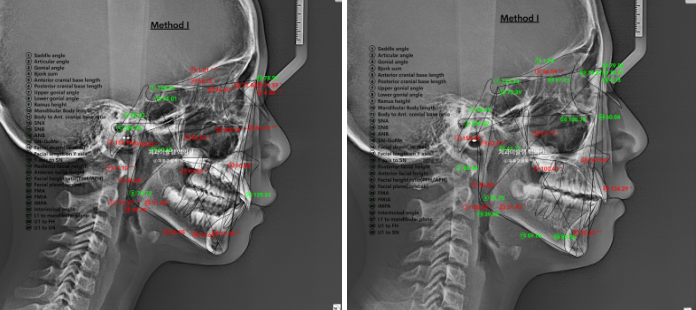

23.06~25.06

처음에 비해 무턱을 나타내는 수치가 6.4에서 4.7로 줄어들었습니다

4.7은 이 나이대에서는 정상범위 입니다.